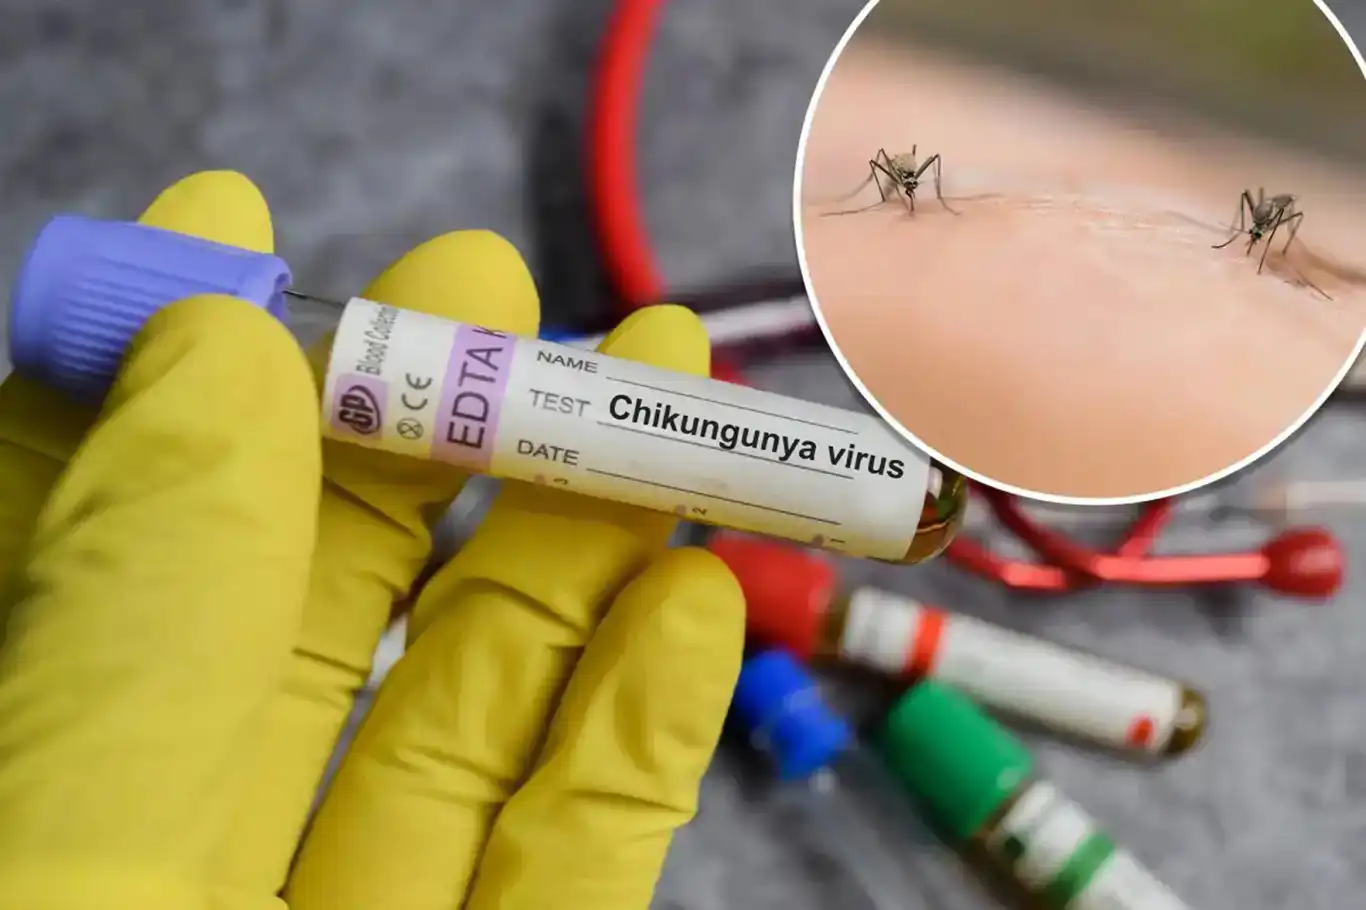

تسجيل حالة إصابة بفيروس شيكونغونيا في الولايات المتحدة

أكدت السلطات الصحية في ولاية نيويورك الأمريكية تسجيل أول حالة محلية لفيروس شيكونغونيا، وذلك للمرة الأولى منذ ست سنوات.

أعلنت السلطات الصحية في ولاية نيويورك عن رصد أول حالة محلية لفيروس شيكونغونيا بعد غياب دام ست سنوات.

وأوضحت وزارة الصحة في ولاية نيويورك أن الفيروس، الذي ينتقل عبر البعوض، تم اكتشافه لدى شخص يقيم في مقاطعة ناسو في منطقة لونغ آيلاند.

ويرجّح الخبراء أن الإصابة حدثت على الأرجح نتيجة تعرض المريض للسعة بعوضة مصابة بالفيروس.

ويُعرف أن نوع البعوض القادر على نقل فيروس شيكونغونيا يتواجد في بعض مناطق نيويورك الكبرى، خاصة في لونغ آيلاند. (İLKHA)